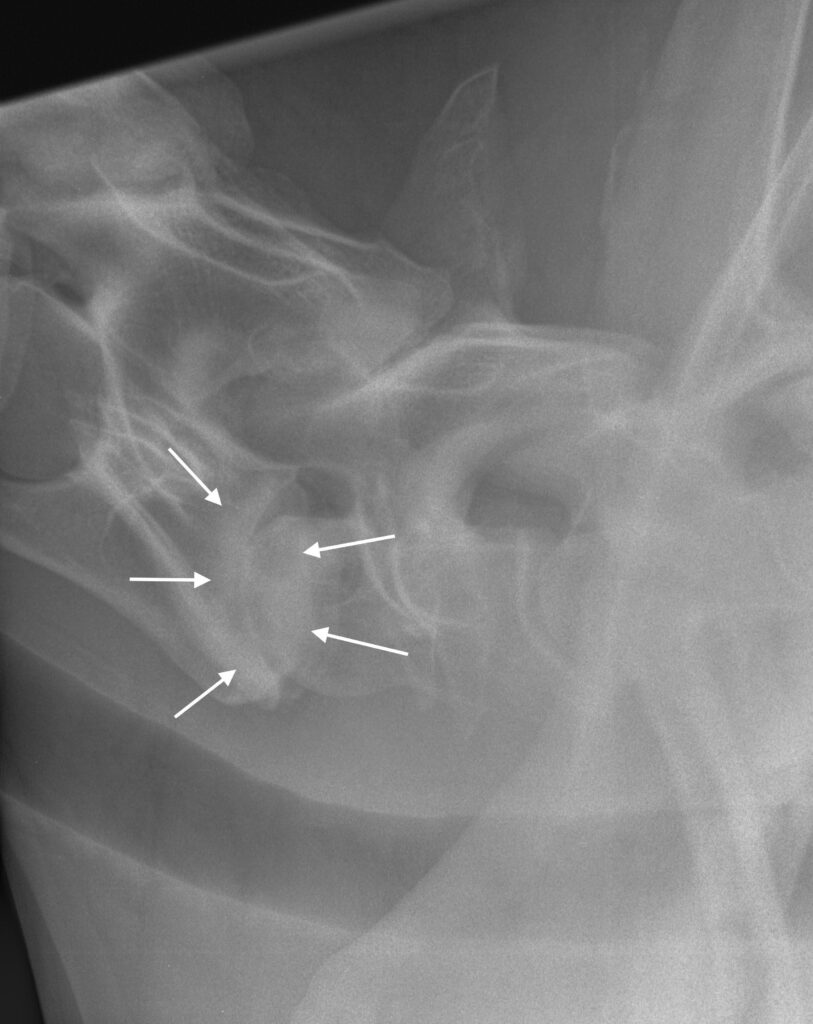

Artróza meziobratlových kloubů (obr. 7 a 8): Pokud dojde ke vzniku artrotických změn na malých kloubech mezi jednotlivými obratli, jednotlivé plošky kloubu zduří, což může vést ke zúžení páteřního kanálu.

Obrázek 7: Rentgen krku koně se závažnou artrózou na úrovni C7–T1; meziobratlová ploténka je téměř zničena a došlo ke zhroucení kloubu (bílé šipky)

Obrázek 8: Kůň na obr. 7 byl ataktický a často docházelo k blokádám krční páteře, proto byla provedena artrodéza C7–T1

Artróza v tomto místě může vzniknout jak přirozeně v důsledku stárnutí koně, tak například kvůli přítomnosti OCD fragmentů (obr. 6). Velmi často se objevují artrotické změny v kloubech krční páteře jako následek předchozího úrazu. Pokud kůň upadne přes hlavu jako roček na pastvině, je možné, že se už u tak mladého koně rozvine artróza krční páteře s nebo bez rentgenologicky detekovatelných kostních úlomků.